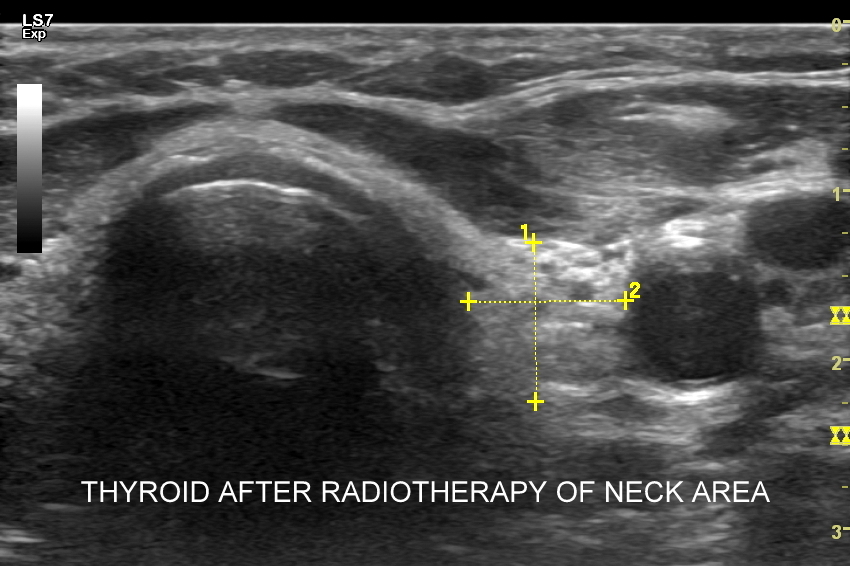

W Interdyscyplinarnej Pracowni USG dr Tomasza Szczepańskiego istnieje możliwość przeprowadzenia wysokospecjalistycznej oceny gruczołu tarczowego w postaci multiparametrycznego badania MPUS tarczycy, które wykonywane jest na zaawansowanym technologicznie aparacie USG przy wykorzystaniu modalności zwiększających rozdzielczość obrazowania zmian chorobowych oraz wnoszących istotne, dodatkowe dane kliniczne dotyczące zmian patologicznych w organie. Badanie MPUS tarczycy jest szczególnie przydatne w przypadku diagnostyki i oceny guzków tarczycy oraz ich kwalifikacji do dalszego postępowania. Nowoczesne modalności MPUS, o których mowa, obejmują w szczególności badanie dopplerowskie miąższu gruczołu, ocenę dopplerowską tętnic tarczycowych, badanie mikroprzepływów  MVF oraz elastografię.

Czy przy USG tarczycy wykonywana jest elastografia? W przypadku stwierdzenia w gruczole stanów patologicznych, np. guzków, a posiadając przy tym aparat USG dysponujący elastografią, można zastosować tenże tryb w celu uzyskania dodatkowych danych medycznych dotyczących wykazanego guzka. Poza elastografią tarczycy ważniejszym dodatkowym trybem obrazowania guzków tarczycy jest tryb mikrounaczynienia MVI.